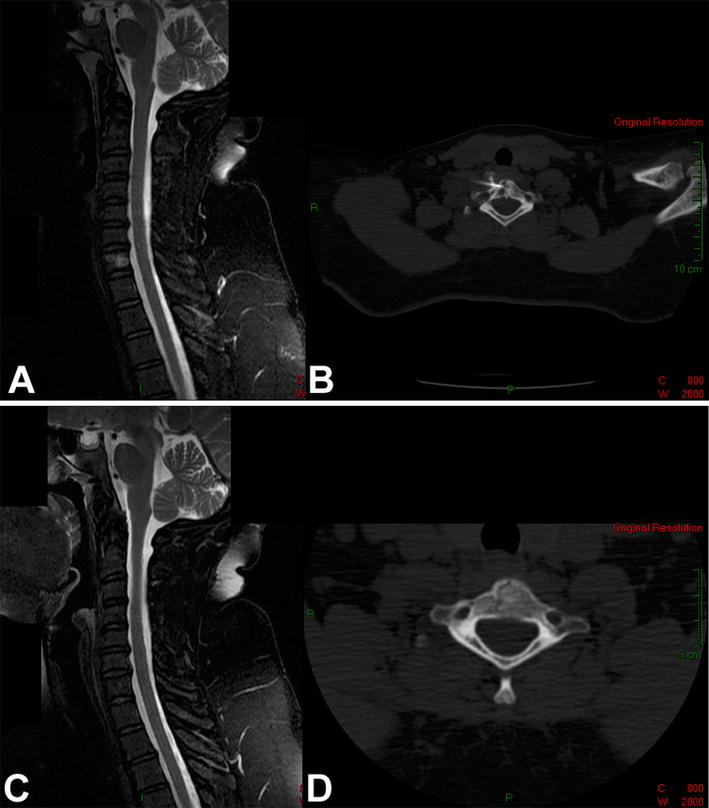

a Sagittal T2-weighted MRI with fat suppression of the cervical spine of a 43-year-old woman with a painful osteolytic lesion of the C7 vertebral body. b CT-guided frozen section biopsy showed eosinophilic granuloma; intralesional methylprednisolone injection was performed. c Sagittal T2-weighted MRI with fat suppression. d Axial CT scan show complete reconstitution of the lesion 4 years after diagnosis and treatment

a Coronal CT scan of the cervical spine of a 5-year-old boy with a painful osteolytic lesion of the C7 vertebral body. b CT-guided frozen section biopsy showed eosinophilic granuloma; intralesional methylprednisolone injection was performed. c, d Sagittal (c)and axial (d) CT scans showing complete reconstitution of the lesion 5 years after diagnosis and treatment